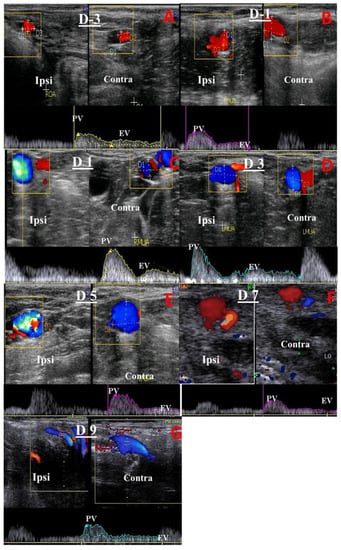

- Hemodynamic changes within the MUA on the ipsi- and contra-lateral sides of the uterine horn at its origin (the internal iliac artery) and within the OA corresponding to the ovarian tissues were monitored as previously reported [29,30] (Figure 2). In brief, once the MUA was visualized via B-mode ultrasonography, blood flow was affirmed using the Doppler device color mode, followed by pulsed-wave mode activation for Doppler index measurement. All calculations were determined automatically by the device and measured three times to obtain the mean by the same person. At least three successive waves (cardiac cycles) were estimated to measure the Doppler parameters with calibrated and fixed Doppler settings throughout the study, as follows: The pulse repetition frequency was 3.5 KHz, the angle of insonation was less than 60 °, and the color flow mapping included two colors (red and blue; Figure 2). Examined blood flow parameters were the pulsatility index (PI), resistance index (RI), peak systolic/end-diastolic ratio (S/D), time-averaged maximum velocity (TAV; cm/s), uterine blood flow rate (BFR; bpm), and uterine blood flow volume (BFV; mL/min). BFV was estimated using the following equation: BFV = TAV(cm/s) × (D(cm) × 0.5)2 × π 60 [22].